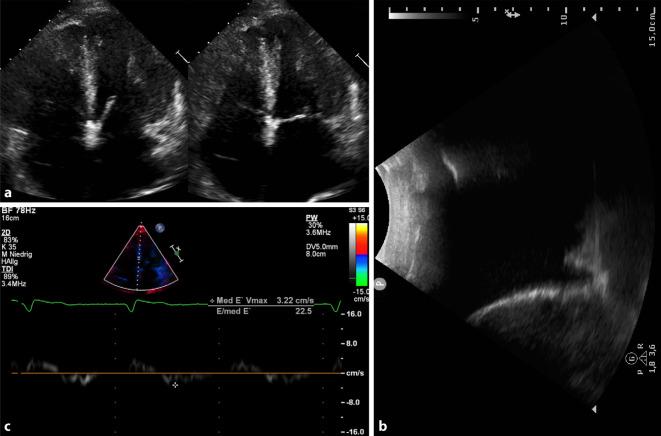

A 79-year-old Caucasian male presented with dyspnea, edema, and weight gain. Echocardiography revealed left ventricular wall thickening and restrictive cardiomyopathy. Bone scintigraphy revealed abnormal cardiac tracer uptake consistent with cardiac TTR-amyloidosis, which could be confirmed by endomyocardial biopsy.

一名79岁的白种男性出现呼吸困难、水肿和体重增加。超声心动图显示左心室壁增厚和限制性心肌病。骨闪烁显像显示心脏示踪剂摄取异常,符合心脏TTR淀粉样变性,这可通过心内膜活检得到证实。